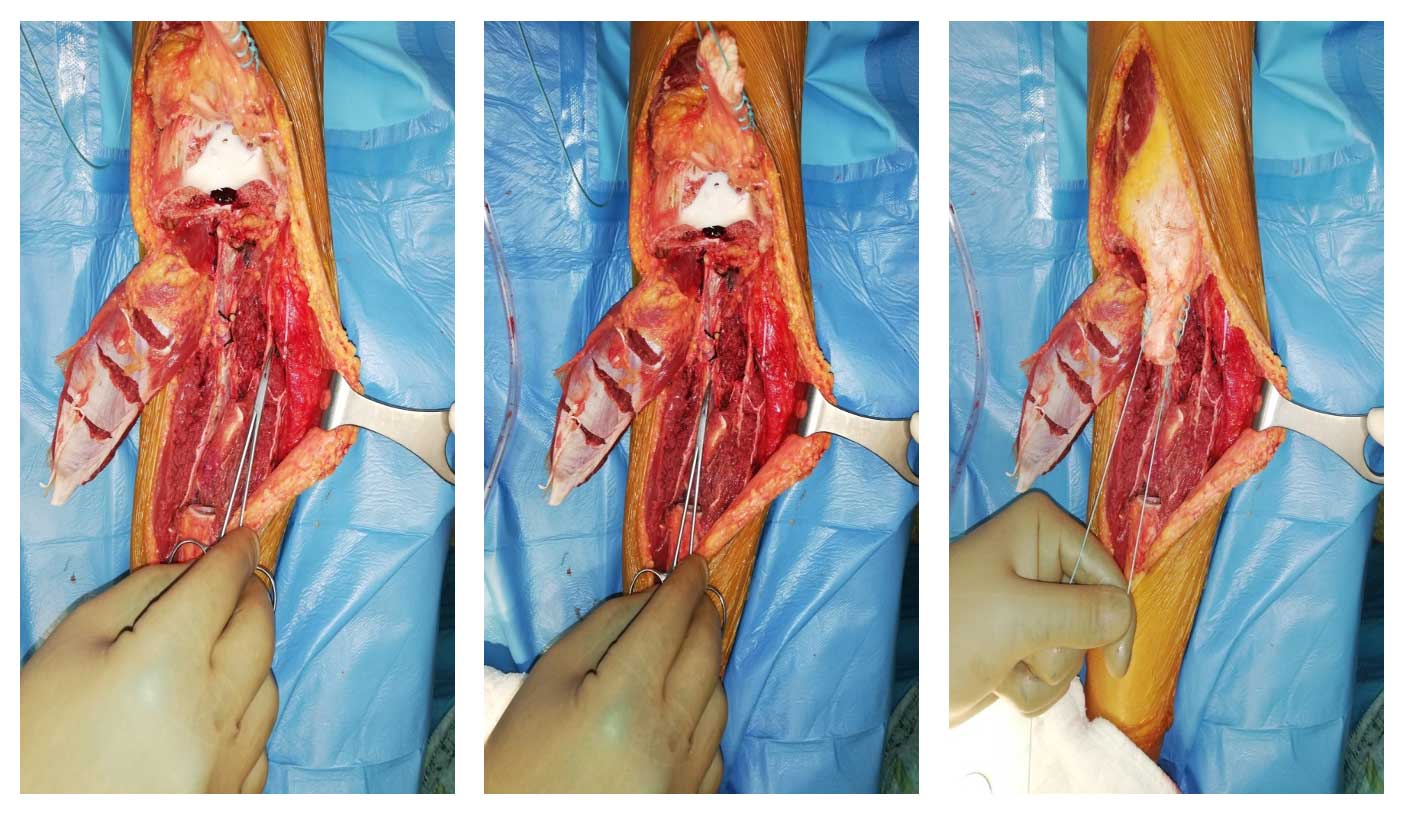

Ameliyat Esnası: Çıkarılan tümör dokusunun klinik ve skopi görüntüsü.

Ameliyat Esnası: Rezeksiyon sonrası, gastroknemius flep hazırlanması, nörovasküler yapıların devamlılığı ve patellar tendon görülmekte.